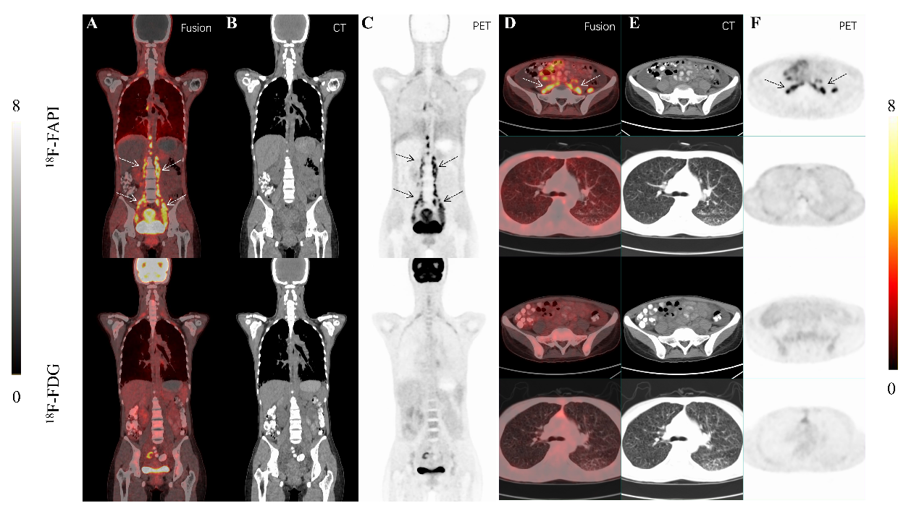

在 79 名来自 64 个 BHDS 家系的患者中,通过遗传检测(排除了意义未明变异后),在 68/79(86.1%)的个体中发现了致病性或可能致病性的 FLCN 基因变异。这些突变位点和类型的分布如图6所示。

图片

图6 64例患者的 FLCN 基因突变情况,其中排除了意义未明的变异。优先显示氨基酸突变位点,若无氨基酸突变位点,则显示核苷酸改变。图中不同颜色代表不同类型的突变:红色:移码突变;黑色:大片段缺失;浅蓝色:无义突变;绿色:缺失突变;深蓝色:错义突变;紫色:剪接位点突变;灰色:点突变

图7 显示了 FLCN 基因突变位点的频率分布。研究发现了一些高频突变热点,具体位点如下:

1.Exon12 (c.1429C>T)

2.Exon14 (c.1579_1580insA)

3.Exon12 (c.1379_1380del)

4.Exon11 (c.1285dupC)

5.Exon9 (c.981del)

图7 64个BHDS家族FLCN基因突变频率